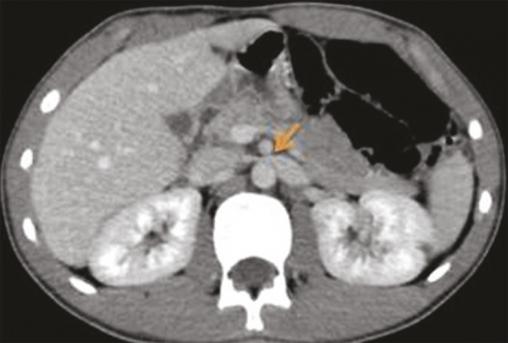

La tomodensitométrie (TDM) a montré une dilatation de la veine rénale de 9 mm, en amont de la pince aortomésentérique (fig. 1) et un matériel hypodense au niveau de la veine spermatique homolatérale, en rapport avec un thrombus (fig. 2).

La tomodensitométrie (TDM) avec injection de produit de contraste objective cette compression de la veine rénale gauche dans la fourchette aortomésentérique, l’angulation entre l’aorte et l’artère mésentérique supérieure (supérieure à 41 °), la distension des veines gonadiques et la congestion pelvienne.2